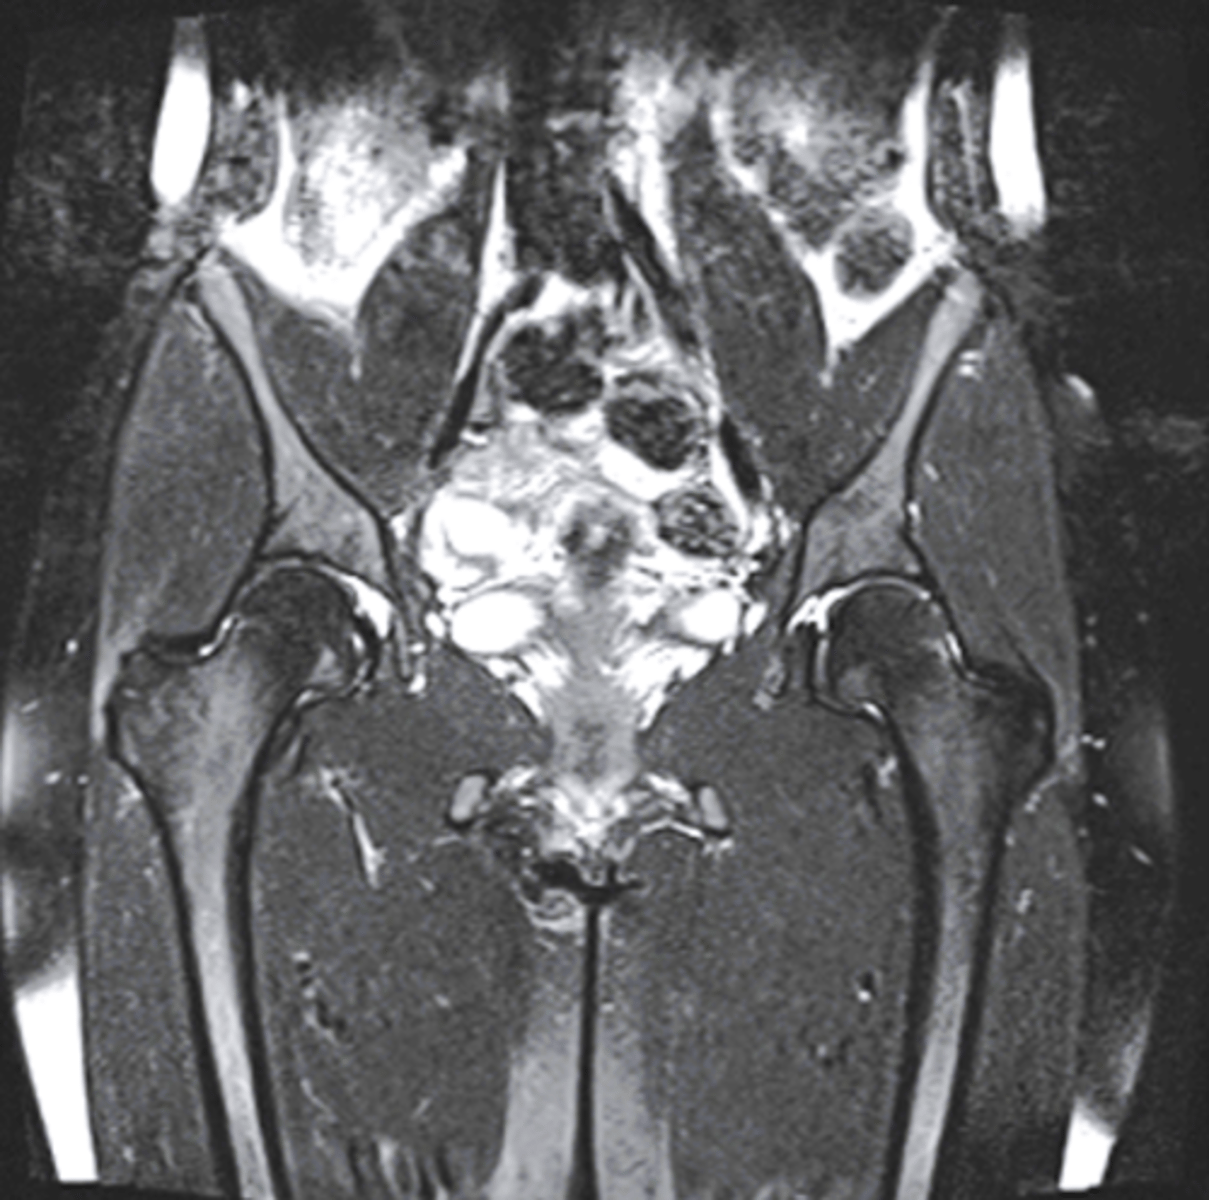

What type of image is shown here of the pelvis/hips?

coronal MRI